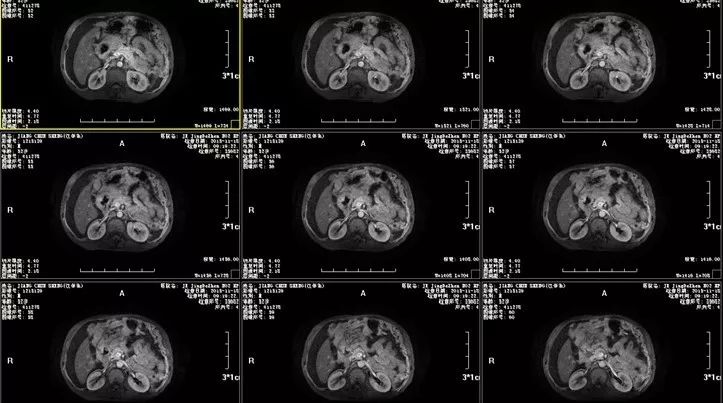

腹水检查仍不能明确病因,接下来行腹部MRI检查,结果示:1.十二指肠球部占位,考虑肿瘤性病变,建议MR增强扫描;2.肝尾叶异常信号影,建议进一步检查;3.大量腹水。

图二 腹部MRI检查图

腹部MRI检查已有阳性发现,紧接着行MRI增强扫描以进一步明确诊断,腹部MRI增强示:1.肝门部及十二指肠球部占位,考虑十二指肠来源恶性肿瘤可能,肝尾叶占位,转移瘤可能,建议进一步检查;2.大网膜及腹膜转移,左侧腹壁转移;3.大量腹水。

图三 腹部MRI增强扫描图